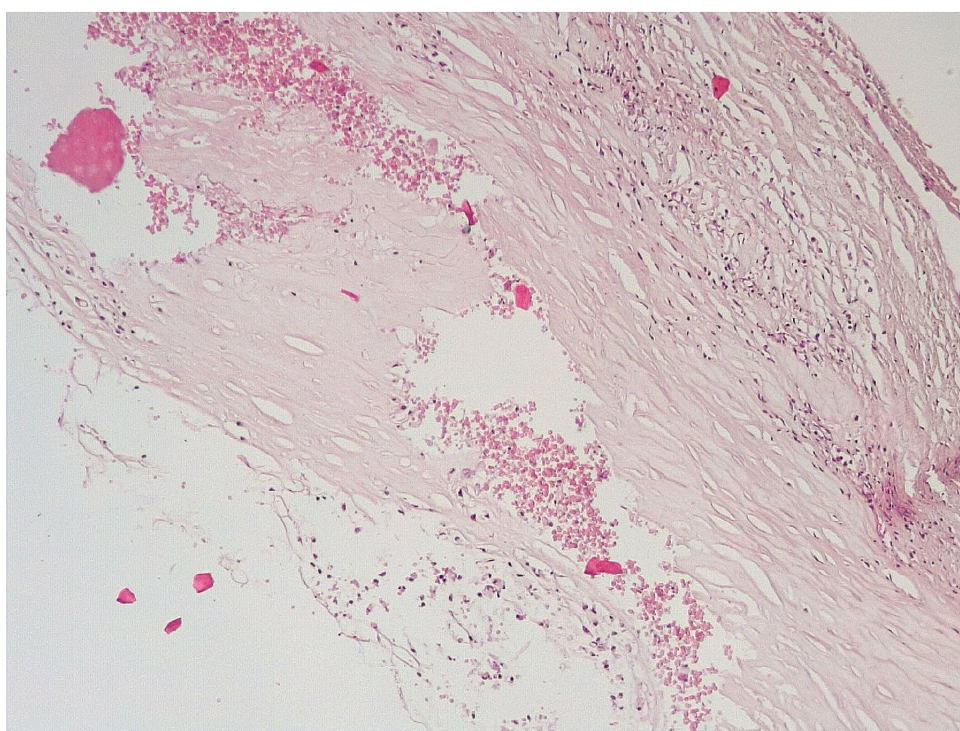

Позднее, спустя 3–7 суток после стентирования КА в просветах имелись пристеночные смешанные фибриново-лейкоцитарные тромбы, которые могли служить источником развития тромбоэмболических осложнений мелких дистальных ветвей коронарного кровотока и развитием острого инфаркта миокарда (рис. 4).

В течение 7–15 суток после стентирования КА наряду с формированием пристеночных фибриновых тромбов с признаками организации в стенках атером наблюдались репаративные процессы, связанные с неоангиогенезом в виде образования мелких тонкостенных кровеносных сосудов капиллярного типа, окруженных мелкими лимфоцитарными, гистиоцитарными клеточными инфильтратами (рис. 6, 7).